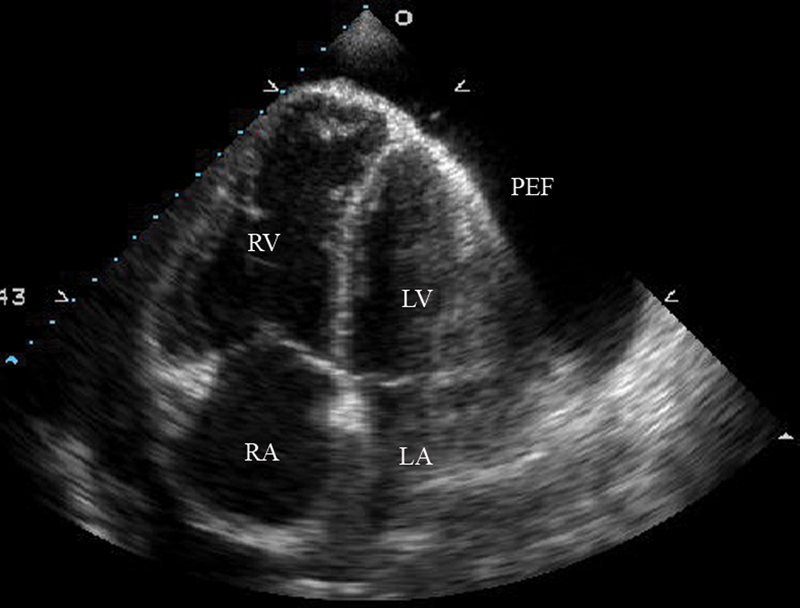

فحوصات تشخيصية لبعض امراض القلب والشرايين التاجية